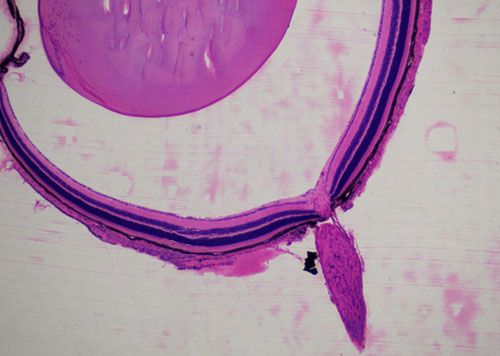

蘇木精-伊紅染色法 ( hematoxylin-eosin staining ),簡稱HE染色法,石蠟切片技術里常用的染色法之一,也可以用于未脫鈣骨硬組織切片。蘇木精染液為堿性,主要使細胞核內的染色質與胞質內的核糖體著紫藍色,伊紅為酸性染料,主要使細胞質和細胞外基質中的成分著紅色。HE染色法是組織學、胚胎學、病理學教學與科研中最基本、使用最廣泛的技術方法。

小鼠眼球硬組織切片HE染色